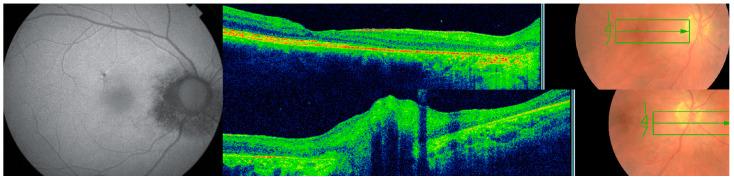

Four cases qualified with the diagnosis of presumed ocular onchocerciasis based on their residence near fast rivers in endemic areas, multimodal imaging, long term follow-up showing progressive disease and negative workup for other diseases. Characteristic findings include peripapillary choroiditis with optic neuritis or atrophy, subretinal tracts of the microfilaria, progressive RPE atrophy around heavily pigmented multifocal chorioretinal lesions of varying shapes, subretinal white or crystalline dots, and response to ivermectin. Typical skin findings are often absent in such patients with chorioretinitis rendering the diagnosis more challenging.

4例患者根据其居住在流行地区的快速河流附近、多模态成像、显示疾病进展的长期随访以及其他疾病检查结果为阴性,被确诊为疑似盘尾丝虫性眼病。特征性表现包括伴有视神经炎或萎缩的视乳头周围脉络膜炎、微丝蚴的视网膜下条索、围绕形状各异的色素沉着多灶性脉络膜视网膜病变的进行性视网膜色素上皮萎缩、视网膜下白色或结晶状小点以及对伊维菌素的反应。此类脉络膜视网膜炎患者通常没有典型的皮肤表现,这使得诊断更具挑战性。